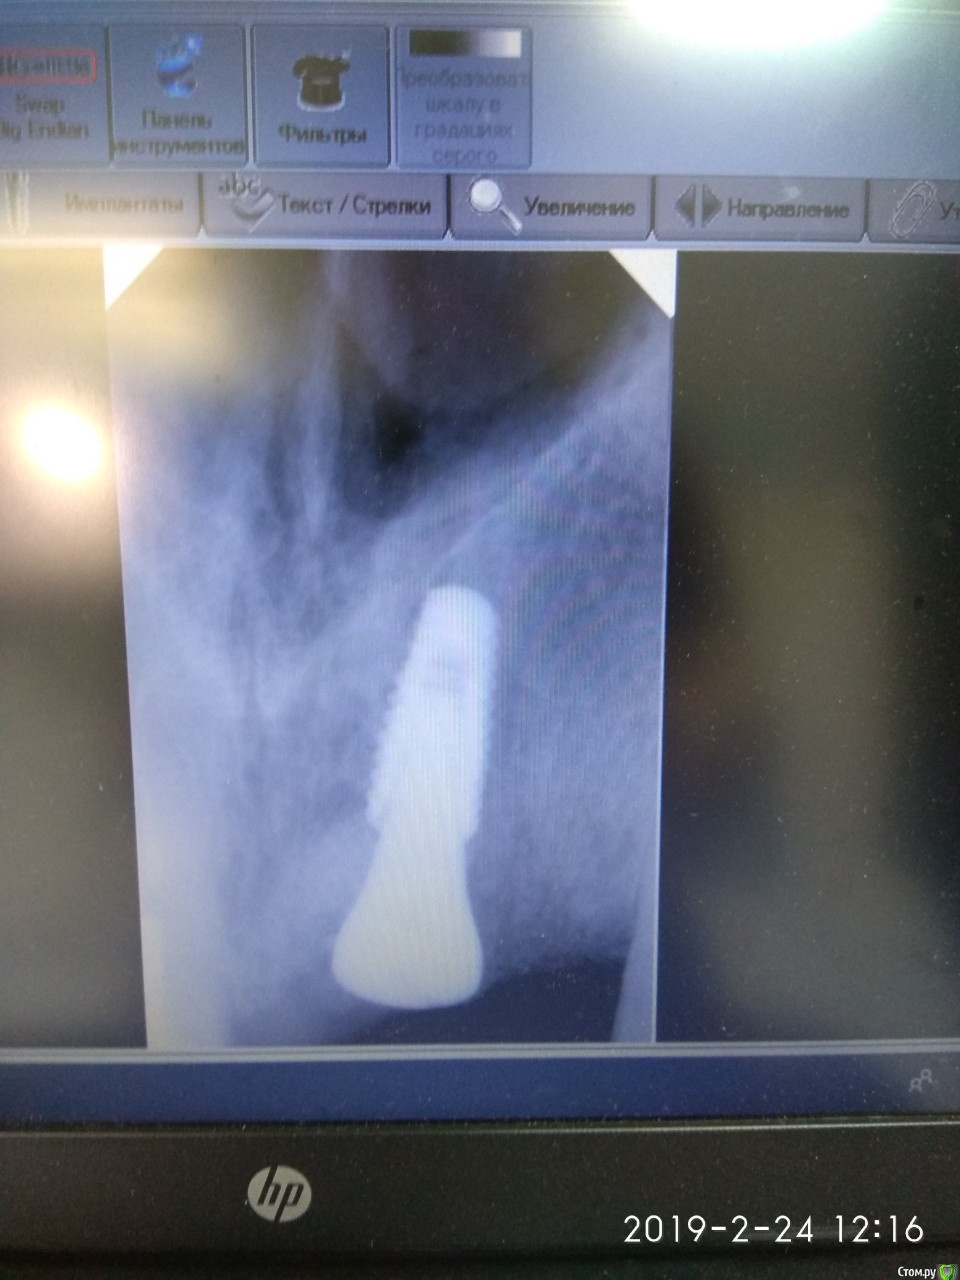

bogdan_r Опубликовано 28 февраля, 2019 Автор Поделиться Опубликовано 28 февраля, 2019 (изменено) Доброго дня. Спасибо всем за советы. Удалил зуб. Почистил грануляции, установил имплантант 4.0*10 Anyone Megagen. Хотел сразу установить формик, а кость была не очень плотная, поэтому заглубил имплантант на 6 мм от уровня десны и 4 мм от небной стенки. Знаю, что глубоко. Может чуть-чуть открутить имплант? Прошло 5 дней. Торк был 25Н Изменено 28 февраля, 2019 пользователем bogdan_r Ссылка на комментарий

bogdan_r Опубликовано 28 февраля, 2019 Автор Поделиться Опубликовано 28 февраля, 2019 Ещё одно фото Ссылка на комментарий

bogdan_r Опубликовано 28 февраля, 2019 Автор Поделиться Опубликовано 28 февраля, 2019 Тут лучше видно Ссылка на комментарий

___49___ Опубликовано 28 февраля, 2019 Поделиться Опубликовано 28 февраля, 2019 Тут лучше видноа вы формиком боковой поверхностью в кость не уперлись ? 1 Ссылка на комментарий

bogdan_r Опубликовано 28 февраля, 2019 Автор Поделиться Опубликовано 28 февраля, 2019 а вы формиком боковой поверхностью в кость не уперлись ? Скорее всего да. А что скажите про глубину? Может чуть-чуть открутить имплантант Ссылка на комментарий

___49___ Опубликовано 1 марта, 2019 Поделиться Опубликовано 1 марта, 2019 (изменено) А что скажите про глубину? кажется глубоко . Может чуть-чуть открутить имплантантконус о приоре чуть- чуть открутить невозможно - он просто вывалится - только если перекрутиться другим имплантом . а в вашем случае единственный вариант чтоб обойтись меньшей кровью - это более узкий ФДМ,но такой подход не очень хорош уже в конкретном случае.... Я вообще к фронтальным имплантам подошел только после учебы по НКР - для меня это пока еще сложнее чем синус или расщепление. Изменено 1 марта, 2019 пользователем ___49___ Ссылка на комментарий